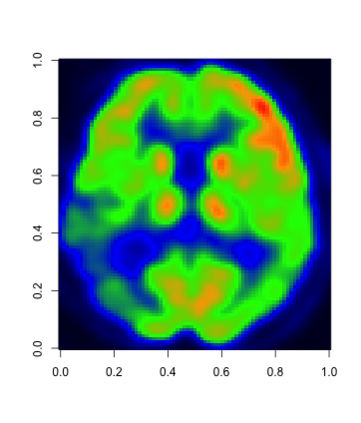

In this paper, we propose a robust estimator for the location function from multi-dimensional functional data. The proposed estimators are based on the deep neural networks with ReLU activation function. At the meanwhile, the estimators are less susceptible to outlying observations and model-misspecification. For any multi-dimensional functional data, we provide the uniform convergence rates for the proposed robust deep neural networks estimators. Simulation studies illustrate the competitive performance of the robust deep neural network estimators on regular data and their superior performance on data that contain anomalies. The proposed method is also applied to analyze 2D and 3D images of patients with Alzheimer's disease obtained from the Alzheimer Disease Neuroimaging Initiative database.